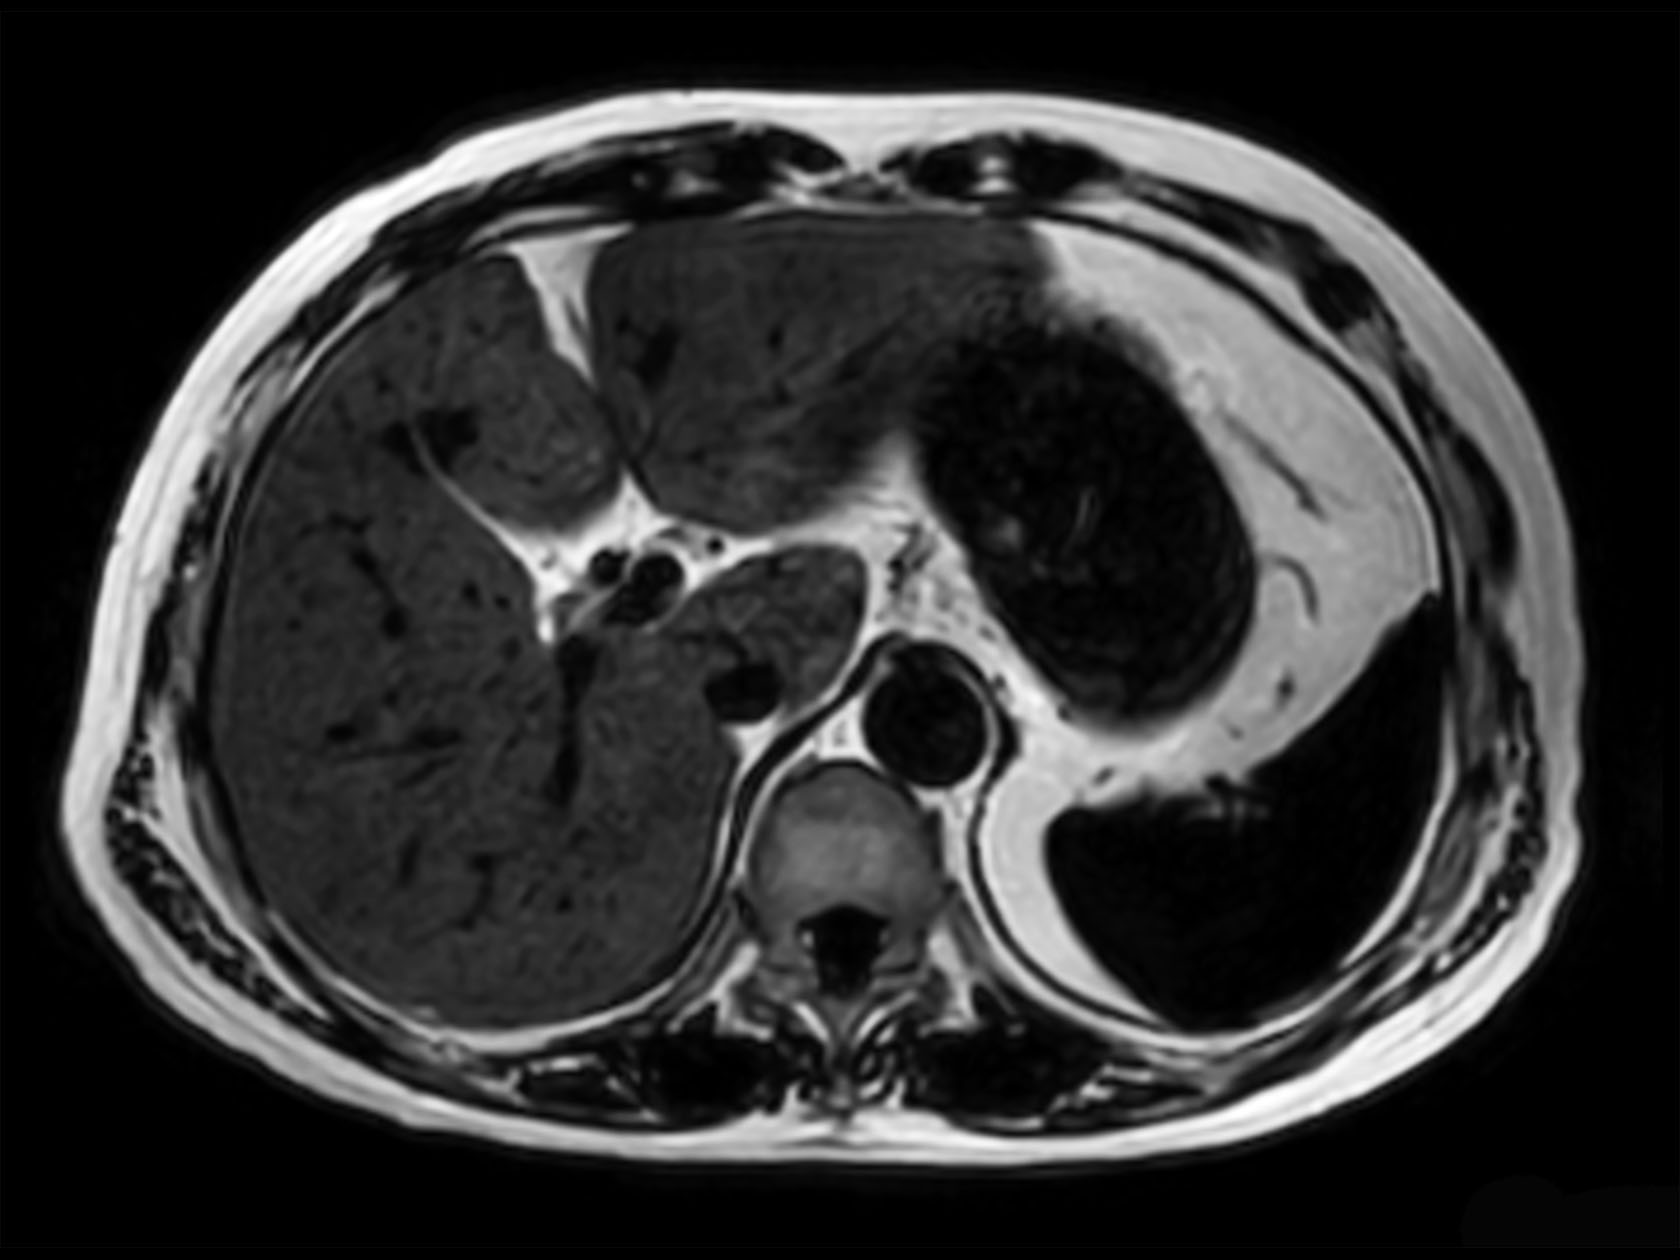

Axial mDIXON XD FFE (Water only)